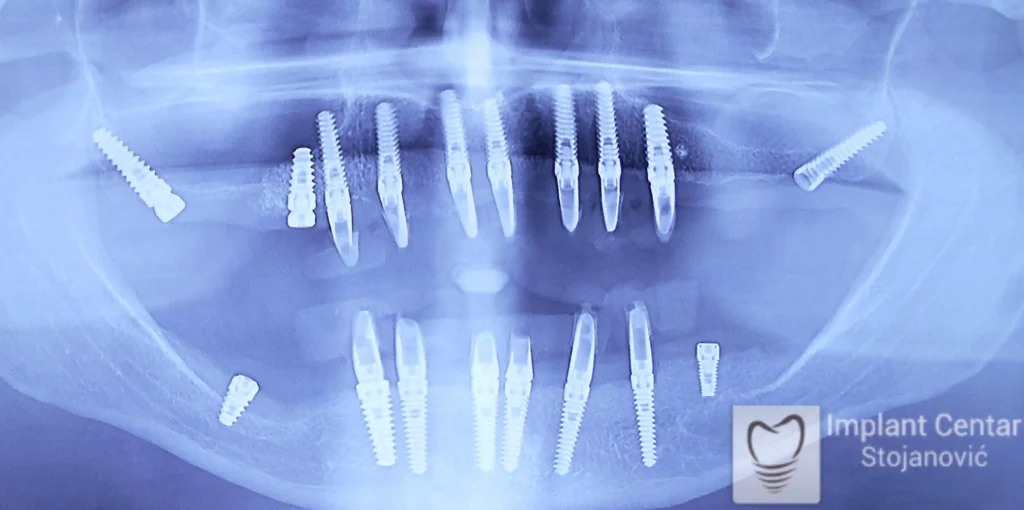

Zbog toga je plan terapije uključivao vađenje svih preostalih zuba i ugradnju implantata u gornjoj i donjoj vilici. U gornjoj vilici postavljena su i dva tuberopterigoidna implantata, kao zamena za sinus lift proceduru, što se može videti na ortopan snimku nurađenom odmah nakon ugradnje (slika 3).

• Ukupno je u gornjoj vilici ugrađeno 10 implantata kako bi se obezbedilo ravnomerno opterećenje pri žvakanju, a u donjoj vilici 8 implantata, što je omogućilo optimalnu stabilnost.